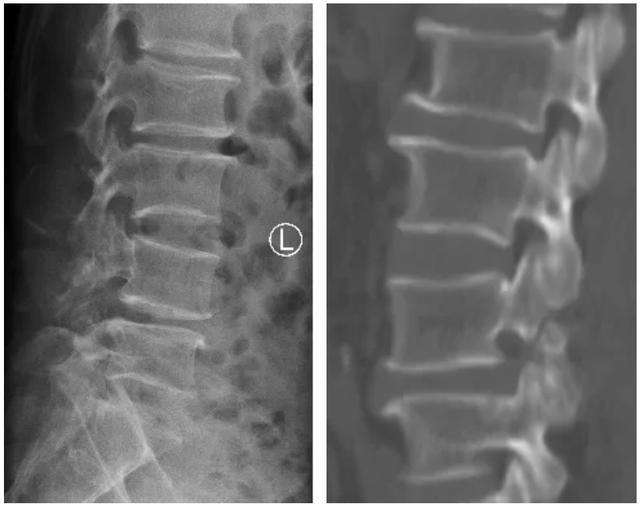

▲术前X线见L4椎体滑脱,CT见L4椎体峡部不连